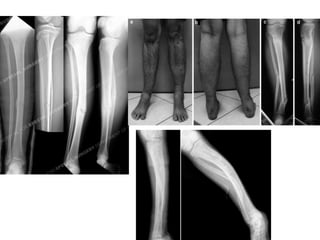

• Axial Deviation

• The bone may bend due to severe muscular forces. These are the commonest

complications due to limb lengthening.

• Its must to prevent these from occurring. A stronger frame, differential turning with

application of hinge etc. can solve this problem. This usually needs modifications to the

frame without anesthesia. Sometimes addition of pins under anesthesia may be

needed as well.

• Tibial lengthenings have to tendency to bend into valgus and procurvatum. This is

due to greater muscle bulk posteriorly and laterally.

• Femoral lengthenings tend to bend into varus and procurvatum.

• Deviations may occur at any stage, including the very last stage of hardening.